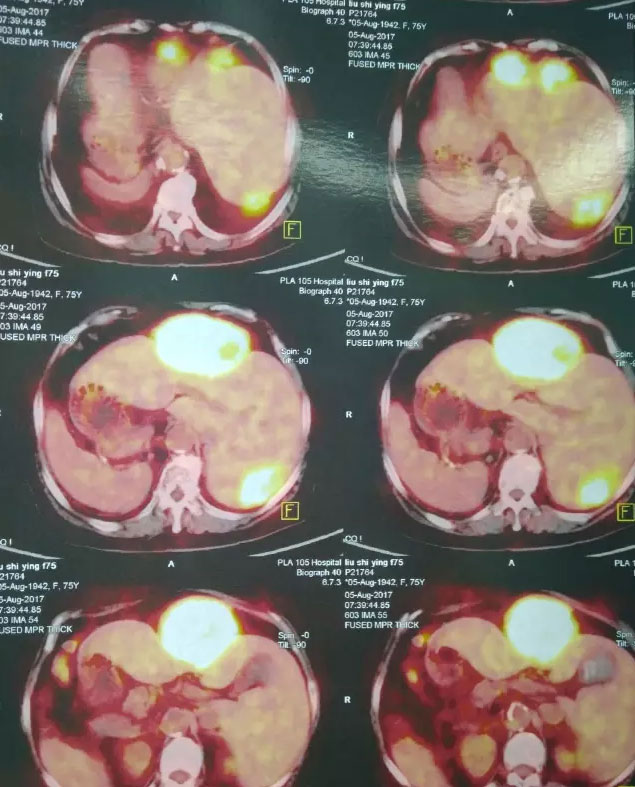

这位病人是75岁的刘老太大,长期居住黄山市,无意发现左侧上腹部“拳头”大小包块伴有隐痛,在当地中医院就诊,检查提示“肝脏多发肿瘤,胆囊内充满结石,右位心,冠心病”。因未接触过如此罕见疑难疾病而建议转上海、北京等上级医院治疗。病人子女在我市工作,抱着一线希望,带着老人来到我院肝胆胰外科。入院后完善相关检查,很快明确了诊断:肝脏IV、VII段两处肿瘤(原发性肝癌),最大的约10cm,胆囊充满性结石伴胆囊炎,冠心病,心律失常,高血压病,器官反位(镜面人)。虽然总院肝胆胰外科有着每年数百例肝胆手术的经验,但如此罕见变异,合并多种基础疾病,高龄的肝脏恶性肿瘤病人,尚属首次接诊,并无成功经验可循。

接诊后,江永强院长高度重视,提请医务处胡伟科长,组织全院疑难肿瘤病人多学科团队(MDT)会诊讨论。多位专家一致认为手术指征明确,但手术难度极高,麻醉管理难度较大,围手术期风险及并发症发生率高。尤其采用腹腔镜微创的方法,更是奇思妙想,大胆创新的思维。普外一科肝胆胰病区徐友标、张军、顾冕三位专家在术前翻阅了大量国内外关于“镜面人”手术的文字和录像资料,积极准备术中突发状况预案,并模拟进行演习。一切充分准备就绪后,手术于8月17日上午进行,徐友标主任亲自主刀,张军、顾冕两位医师配合,麻醉科刘伦主任主麻。术中在病人腹部五处布孔(每个孔约0.5-1cm)。徐主任采用反向操作及反手游离,经过三个小时紧张细致的操作,成功为病人实施“腹腔镜下肝脏IV、VII段两处肿瘤切除+胆囊切除术”。术中失血极少,麻醉平稳,病人在SICU(外科重症监护室)过渡一天后,即转回肝胆胰病房。次日刘阿姨已经进流质饮食,并可以适当活动,微创手术带给她的术后疼痛感觉微乎其微,刘阿姨和子女都难以相信,经历了如此高难度的大手术。